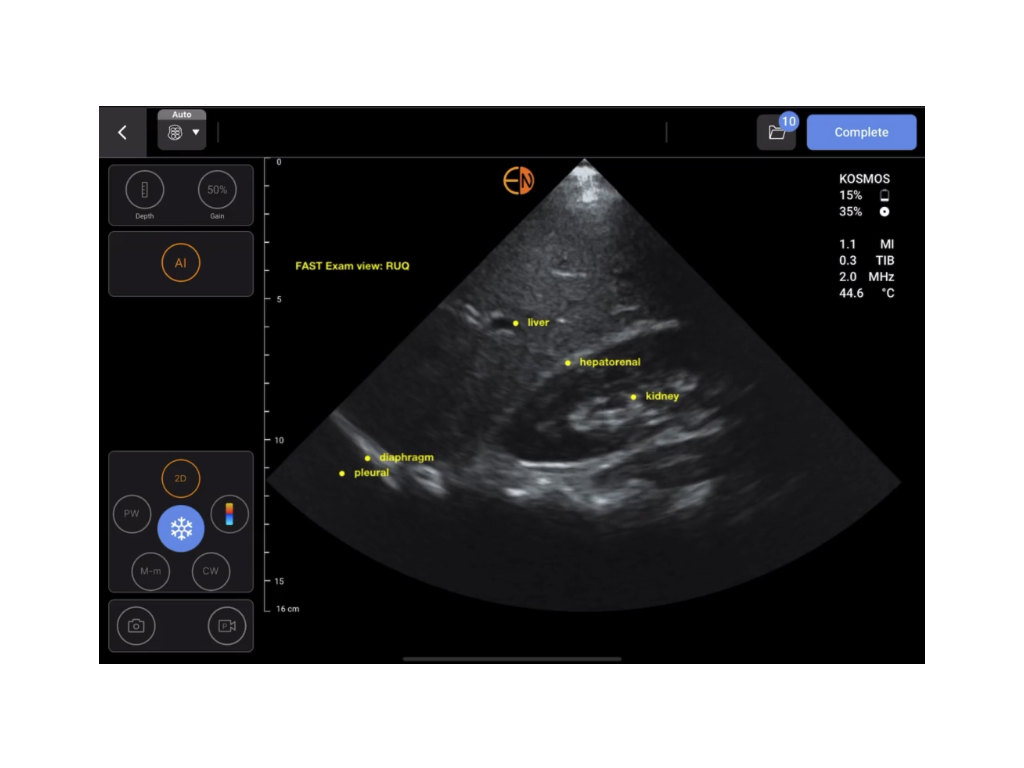

AI Fast